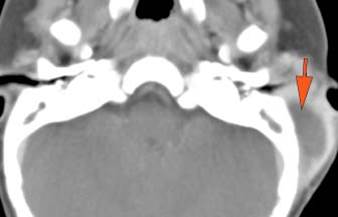

There is edema%2fcellulitis surrounding the pinna, periauricular soft tissues, parotid gland or masticator and parapharyngeal spaces on either side.

There is a subperiosteal abscess along the outer margin of the mastoid portion of the temporal bone.

There is evidence of thrombosis, thrombophlebitis or other occlusive or inflammatory process of the sigmoid sinus, transverse sinus, the vein of Labbe’ or jugular bulb

There is evidence of thrombosis, thrombophlebitis or other occlusive or inflammatory process of jugular vein.